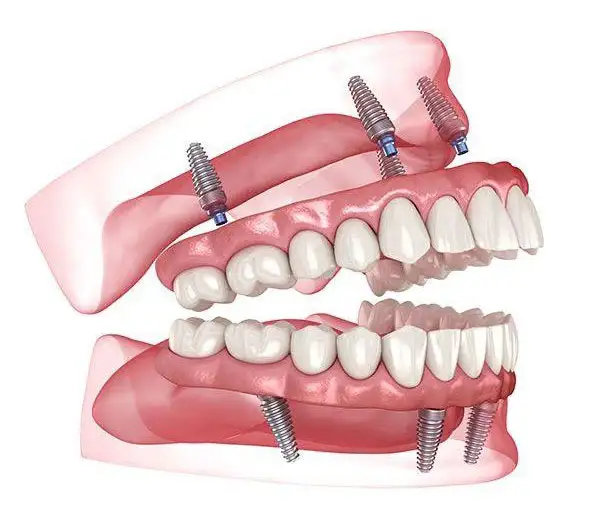

6. Dental Implants

Permanent replacement for missing teeth using high-quality titanium implants that integrate naturally with the jawbone. They function and feel just like natural teeth, allowing you to eat, speak, and smile with complete confidence.

Dental implants preserve jawbone health, prevent facial sagging, and maintain your natural facial structure. They do not affect neighboring teeth and provide a strong, stable, and long-lasting solution for missing teeth. With proper care, implants can last a lifetime, making them the gold standard in modern tooth replacement.